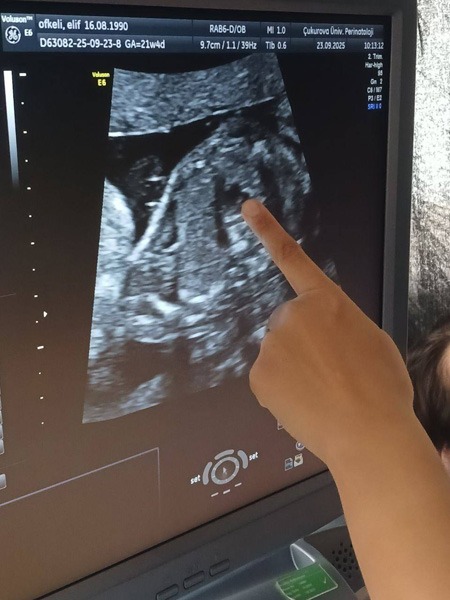

Протягом навчання студенти проходили клінічні ротації на базі двох провідних медичних закладів міста — Університетської лікарні Balcalı Hospital та державної лікарні Yüreğir Devlet Hastanesi. Основний акцент було зроблено на формуванні практичних компетентностей, удосконаленні клінічних навичок і роботі в мультидисциплінарних командах.

Студенти відзначили високий рівень цифровізації турецьких лікарень, активне використання сучасних систем візуалізації та діагностики, а також чітко структуровані клінічні алгоритми ведення пацієнтів. Особливе враження справили ефективна комунікація з пацієнтами та оперативність прийняття рішень у критичних ситуаціях.